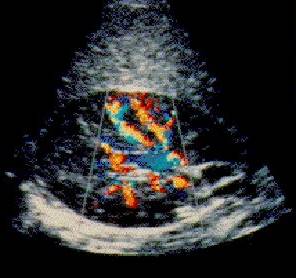

An ultrasound camera is used to record the reflection of a high frequency (1-15MHz) sound bundle, which can be generated and collected by a transducer. One can determine the reflection (amount of reflected sound), depth (from the time taken to receive a reflection) and movement (by Doppler effect) properties of the objects. This is frequently used for medical applications and inspection of the inside of a fabricated product (such as a car engine). The included image (The Burwin Institute) is of a healthy kidney; the color shows the speed of blood moving through the veins. For more information about ultrasound see Medical Ultrasound Imaging WWW Directory. Sonar works much the same.